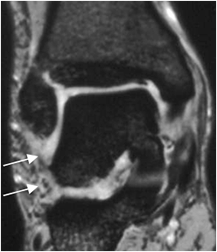

Fig 64 C. Esguince G III.

RM coronal en STIR. No visualización de los ligamentos peroneoastragalino, ni peroneocalcaneo, por ruptura completa.